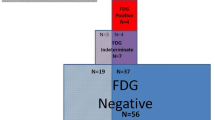

Before the procedure (T0) all patients underwent a diagnostic work-up comprehensive of clinical evaluation, 12-lead ECG, implantable cardioverter defibrillator (ICD) interrogation, trans-thoracic echocardiography and PET scan. A PET scan as well as a comprehensive clinical and echocardiographic evaluation to assess response to immunosuppressive therapy was repeated at 3–6 months (T1). Clinical, echocardiographic and PET data at the last available follow-up (TFUP) were also collected. Basing upon changes of FDG activity on serial PET imaging, patients were categorized into metabolic response (defined by a decrease in the LMA of at least 25%) or non-response (decrease less than 25% or increase). In order to compare LMA to standard calculation of SUVmax and SUVmean as prognostic marker, we used the same criteria to define metabolic response/non-response according to changes in SUVmax or SUVmean. The agreement between different modalities to define metabolic response was assessed using Cohen’s Kappa coefficient. Cardiac death, heart transplant, sustained VT recurrences (defined as any sustained VT on ICD interrogation or 12-lead ECG) and hospitalizations for heart failure were defined as major adverse cardiac events (MACE).

Twenty consecutive patients (51 ± 9 years, 14 males) with diagnosis of CS based upon HRS criteria were included in the study [10]. All patients were evaluated with PET, echocardiographic and clinical examination at T0, T1 and TFUP. All the patients underwent at least three PET scans (T0, T1 and TFUP), and eight (40%) had more than three serial scans (range 3–10). In total, 92 scans were performed. All the patients were treated with immunosuppressive therapy with prednisone (mean daily dose: 40 ± 13 mg). Methotrexate (mean weekly dose 10 ± 3 mg) was added in 6 cases (30%) as a second-line therapy. Eleven out of 20 (55%) patients had evidence of metabolic response while in the remaining 9 (45%), FDG uptake was unchanged or increased. Clinical data of all patients and comparison between “responders” and “non-responders” at baseline (T0) are summarized in Table 1. No significant differences in baseline characteristics were noted between patients with metabolic response compared to those that did not respond.

The median follow-up of the study population was 35 (20–66) months. During this period, one patient (5%) died, two (10%) had heart transplant, 12 (60%) experienced sustained VT recurrence and 3 (15%) were hospitalized for heart failure worsening. Overall, 12 (60%) patients reached the composite endpoint of MACE; 10 (91%) in the metabolic non-responders group and 2 (22%) in the metabolic responders group (p = 0.005). Metabolic responders had a significantly lower proportion of VT recurrences in comparison to non-responders (22 vs. 91%, p = 0.005). A trend towards better outcomes among responders was observed also for death (0 vs. 9%, p = 1.000) and hospitalizations for heart failure (0 vs. 27%, p = 0.218).